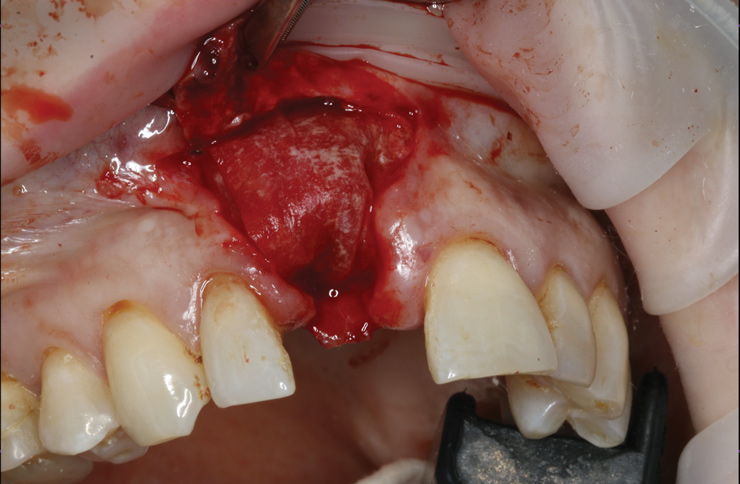

(16.) Full-thickness flap elevation to expose the tenting screw and gain access for anticipated additional bone grafting following implant placement.

Figure 16

(17.) Implant placed 1-mm distal to the midline of the edentulous space, corresponding with the planned location of the gingival zenith. Note the lack of sufficient bone buccal to the implant that necessitated further grafting.

Figure 17

Prior to the initiation of the surgery, the surgical guide was tried in to confirm proper seating and stability (Figure 15). A flapless approach was not considered because the need for further bone grafting at the time of implant placement had been anticipated through the digital planning. A slightly palatal crestal incision was made, followed by two vertical incisions on the mesial and distal aspects of the edentulous site in order to preserve the papilla and avoid additional esthetic compromise to the anterior sextant. Next, a full-thickness flap was elevated to facilitate removal of the tenting screw and permit visualization of the buccal plate (Figure 16). A standard guided protocol was followed to place the implant, and its final position mirrored that of the digital plan. As predicted, the prosthetically driven implant position resulted in an insufficient buccal plate (Figure 17); therefore, additional guided bone regeneration was performed to reinforce the area and prevent future breakdown (Figure 18 and Figure 19). Making periosteal incisions could have compromised the blood supply to the flap, so instead, it was stretched in order to achieve tension free coronal advancement.31The flap was secured utilizing horizontal mattress sutures with additional supportive interrupted sutures to ensure primary closure (Figure 20). An immediate postoperative periapical radiograph (Figure 21) and CBCT scan (Figure 22) were taken, demonstrating a final implant position centered with the planned location of the gingival zenith.